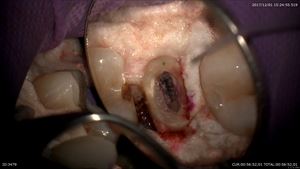

マイクロスコープ治療による精密根管治療

腐った神経が、、、、、

丁寧に汚染物を取ります。

んんんんんんん!!!!!!根管内に何か見える白いふわふわしたもの

綿栓!!!!(歯科医が使う治療用綿)8年間これが原因だったんですね。患者さま驚いていました。

8年分癒着をおこしていて大変でしたが綺麗に。